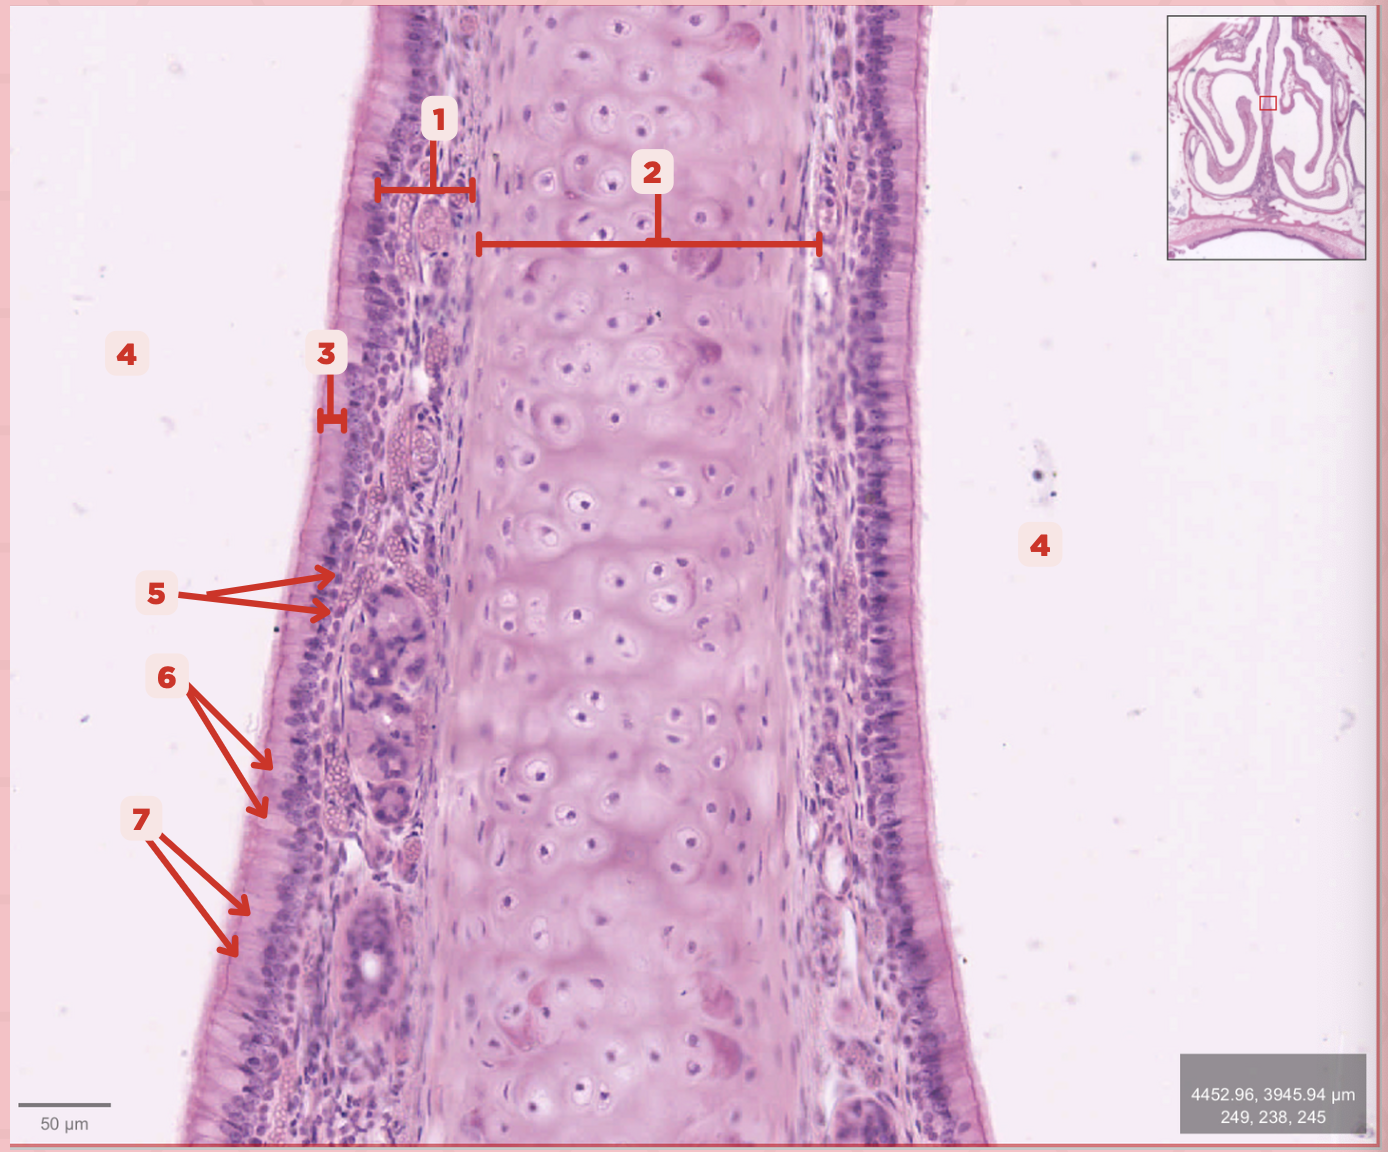

Identify the structure labeled as 1.

Hyaline Cartilage

Identify the structure labeled as 2.

Respiratory Epithelium

Identify the structure labeled as 3.

Nasal Cavity

Identify the structure labeled as 4.

Basal Cells

Identify the structure labeled as 5.

Goblet Cells

Identify the structure labeled as 6.

Ciliated Columnar Cells

Identify the structure labeled as 7.

Adipose tissue

What type of tissue is sometimes seen between the bony spicules?

Serous and Mucous Glands

What glands are present in the Lamina Propria?